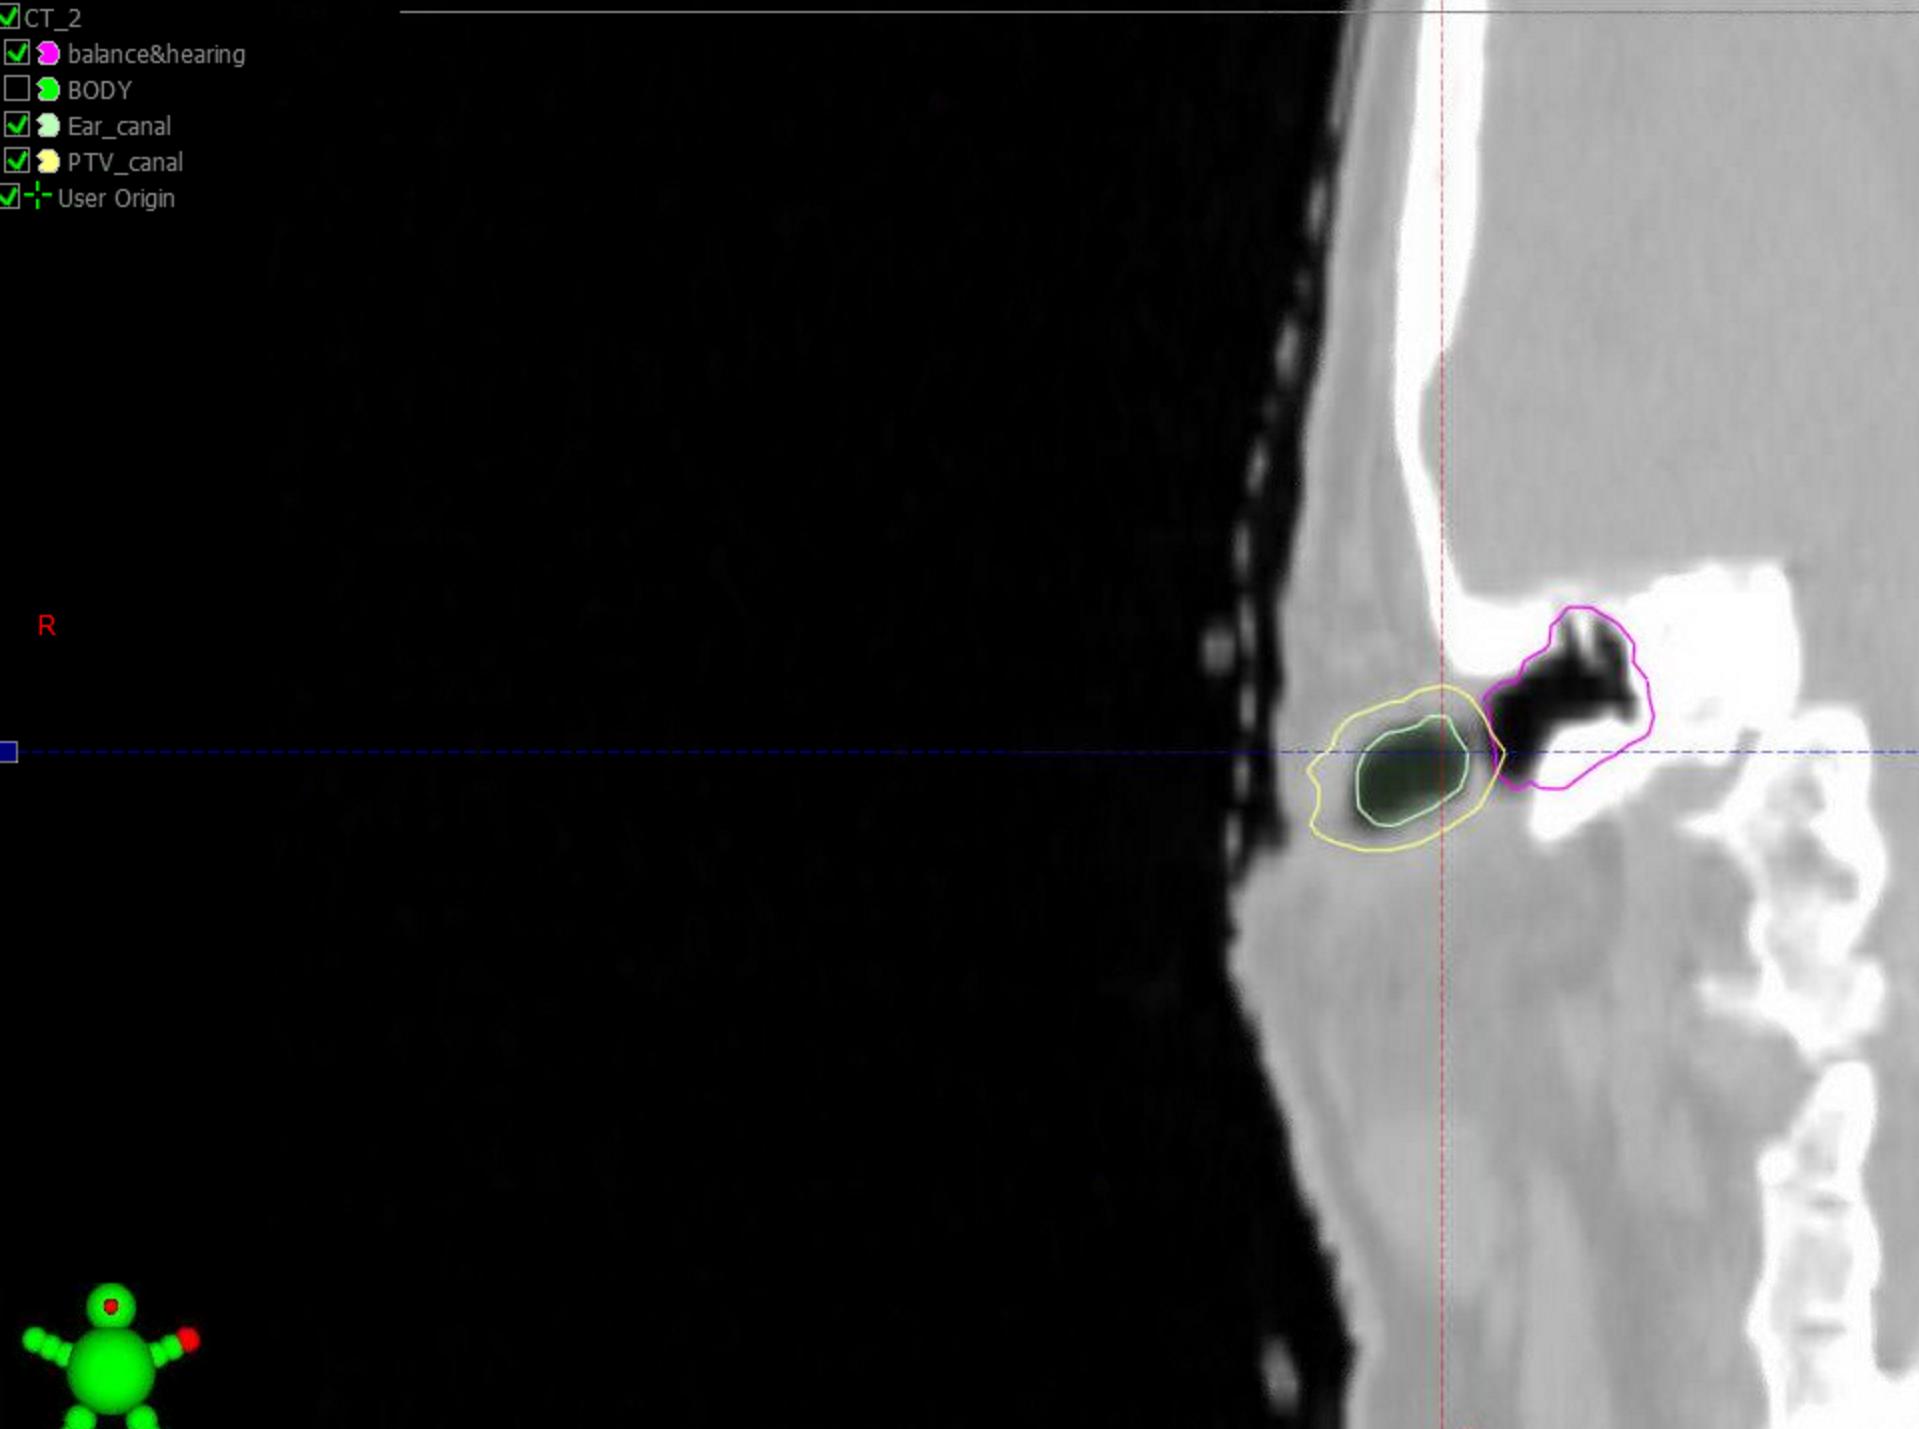

And "hear" is how to treat an ear canal and not risk any hearing loss. Hypothetical case. Ear canal contoured all the way back to TM, and margin (PTV 3mm) on that. Purple is most of the middle/inner ear. Added cochlea after (red). Didn't contour eyes, brain, brainstem; no need.

Rx: 66/33

Needs a little normalization tweak, and this is two summed plans; but still 13 beams only total (all will get a "double shot" the way I planned it).

No hearing loss. No bad moist desqu of external ear. If you trimmed away from the TM a little would all obv look even better.